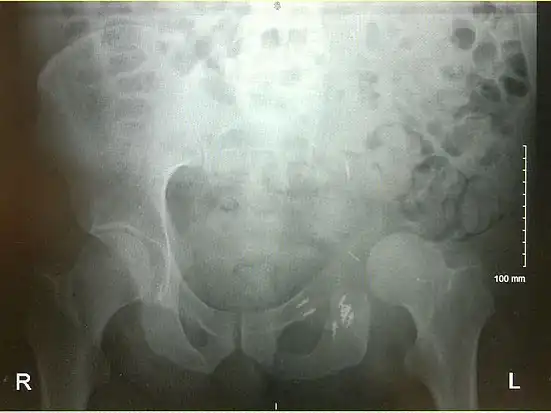

- An x-ray of a limb-sparing hemipelvectomy on the left side of a male pelvis taken one month after surgery.